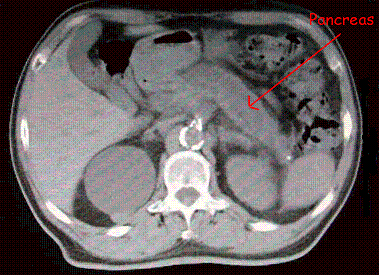

What structure is this?

This structure is the pancreas.